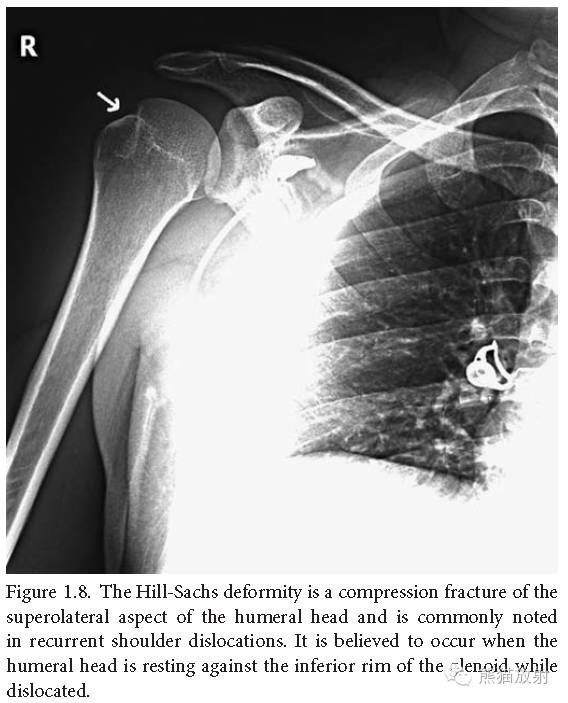

Hill-Sachs畸形:肱骨头外上部的压缩性骨折,常见于反复发作的肩关节脱位,由于脱位时肱骨头靠在关节盂下缘所致。